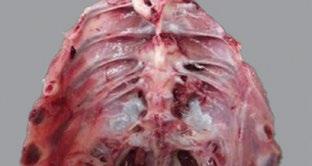

Inicialmente, el área que rodea el tendón roto — generalmente se observa en el tendón gastrocnemio, por encima del tarso— cambia de color, se vuelve de color rojizo - púrpura por la hemorragia, y luego, pasa a verde (Figura 3)

Figura 3. Tendones rotos: (A) color verdoso, (B) tendón roto (hemorragia), (C) tendón roto expuesto.